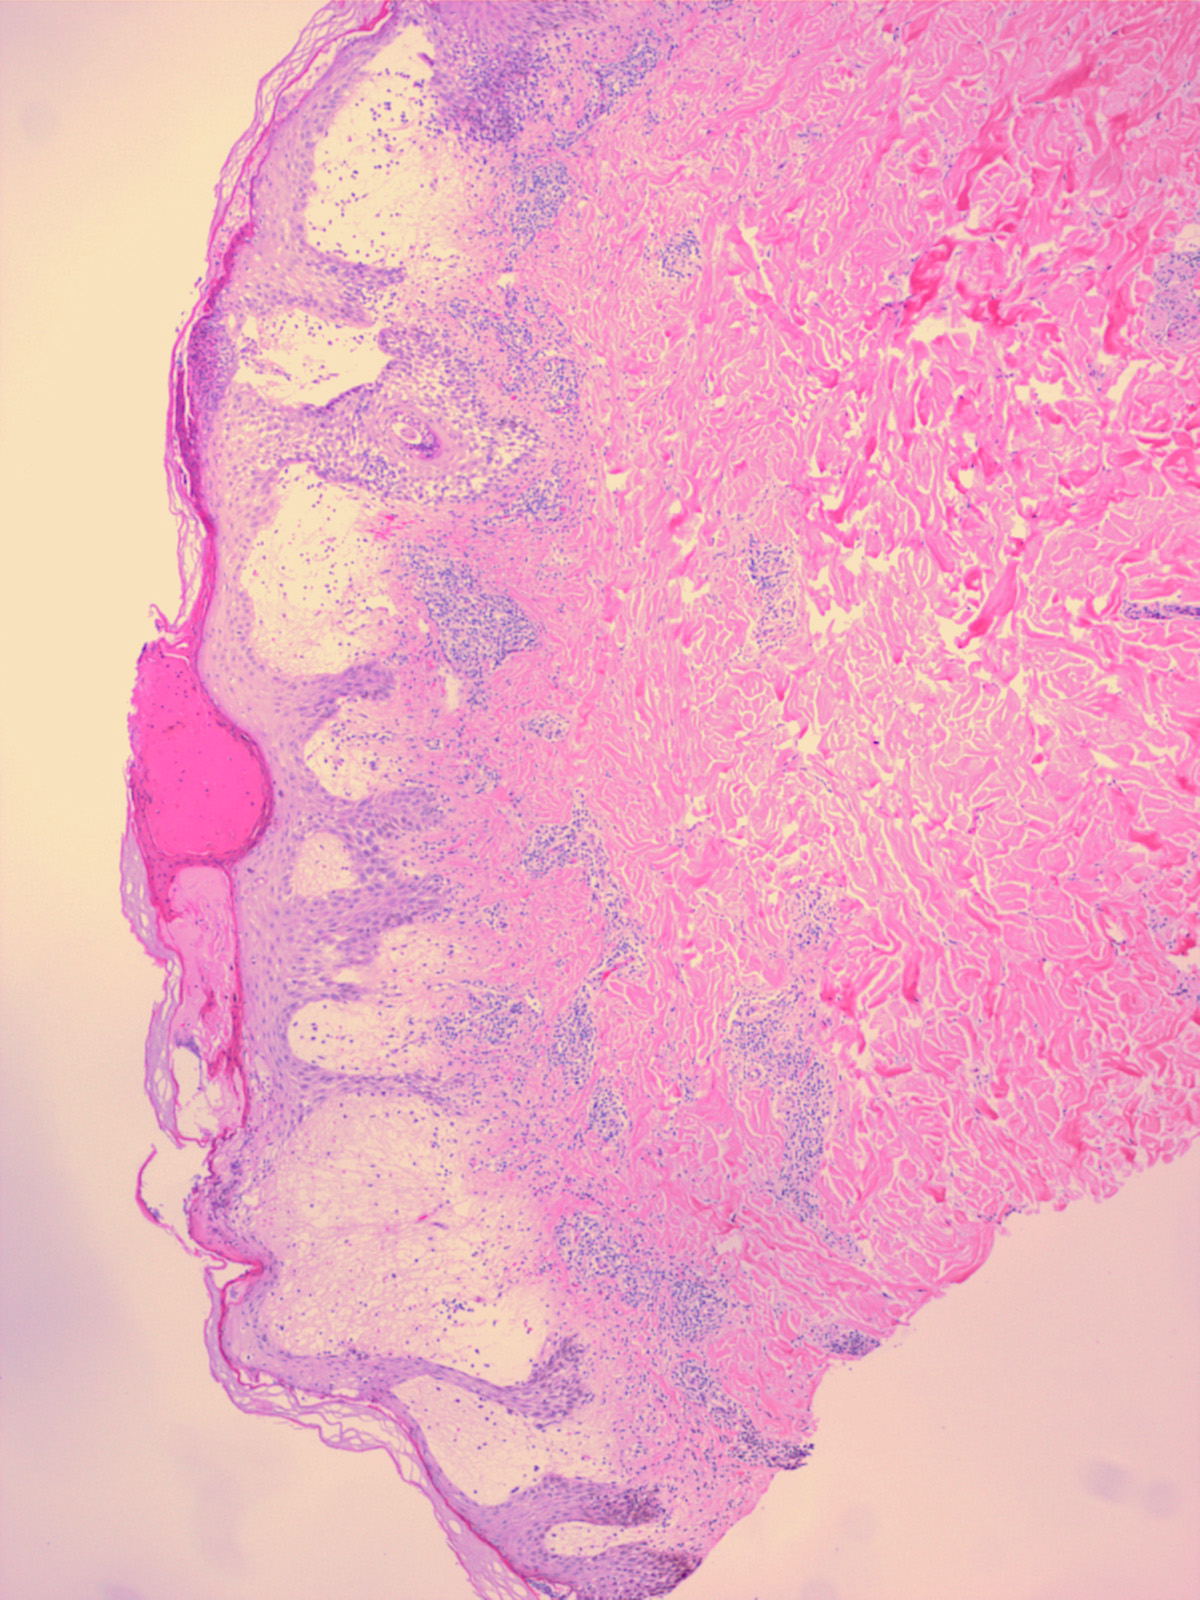

Histopathology The histologic findings vary according to the age of the lesion sampled. Very early lesions show either a normal epidermis or mild spongiosis with focal lymphocyte exocytosis and an underlying mild or occasionally moderate, superficial and deep, perivascular and periadnexal, lymphohistiocytic inflammatory cell infiltrate the lymphocytes have a T-helper phenotype (CD3/CD4 positive). Interestingly, in experimentally induced PMLE lesions, the infiltrate in the first 72 hours postinduction also has a predominant T-helper phenotype but thereafter a mainly T-cytotoxic type (CD3/CD8 positive) . Occasional eosinophils and rare neutrophils may also be found. As lesions progress, there is marked edema of the papillary dermis and more prominent dermal inflammation

in such cases, the histologic picture may resemble cutaneous lupus erythematosus (see next section). Exceptionally, a fairly prominent dermal infiltrate may raise the possibility of lymphoma. In a few cases, the histologic findings may be minimal despite the presence of prominent clinical changes . Pathogenesis. The eruption of PMLE is induced by exposure to UVR, particularly from strong summer sunlight (2,3). Artificial reproduction is less easy, and exact action spectra have not been conclusively determined. Nevertheless, broadly speaking, the responsible wavelengths appear to be UVB in around half of patients and ultraviolet A (UVA) in three quarters, which includes both in one quarter, while visible light has also rarely been incriminated. The eruption itself appears very likely to be a DTH response in view of its pattern of dermal cellular infiltration, cytokine production, and adhesion molecule expression, arguably to UVR-induced, endogenous, cutaneous autoantigen. Further, it appears that a genetically determined impairment of the normal UVR-induced suppression of induction, but interestingly not elicitation, of DTH reactions in the skin is responsible . Differential Diagnosis. The diagnosis is generally apparent from the clinical history, in which sun exposure is nearly always clearly incriminated in causing the typical eruption, provided that the circulating antinuclear and extractable nuclear antibody titers and urinary, stool, and blood porphyrin concentrations are normal. Histologically, PMLE must be differentiated from lupus erythematosus, the porphyrias, AP, Jessner’s lymphocytic infiltrate, cutaneous T-cell lymphoma, chilblains, and rosacea . In cutaneous lupus erythematosus, the interface change is more prominent not only in the epidermis but also in adnexal structures, apoptotic keratinocytes are often seen, and papillary dermal edema is not a feature. In addition, dermal mucin deposition may be seen in lupus and is absent in PMLE. AP usually displays changes secondary to excoriation, variable epidermal hyperplasia, and more prominent lymphocyte spongiosis and exocytosis; however, early lesions in both conditions may show very similar microscopic findings, except that dermal edema is usually absent in AP. In Jessner’s lymphocytic infiltrate, epidermal changes are absent, there is no papillary dermal edema, and the dermal mononuclear cell infiltrate tends to be more prominent. Cutaneous T-cell lymphoma is only rarely included in the differential diagnosis of PMLE, mainly when the dermal infiltrate is prominent; however, the exocytosis of lymphocytes with irregular nuclear outlines is not a feature of the latter, which usually also shows variable spongiosis. The histology of chilblains is almost identical to that of PMLE, particularly when there is prominent papillary dermal edema, but fortunately the clinical setting of each disease usually allows distinction. Rosacea shows no epidermal change, dermal edema is absent, the dermal infiltrate is mild and surrounds superficial small blood vessels and adnexal structures, and focal lymphocytic exocytosis into hair follicles is often seen. |